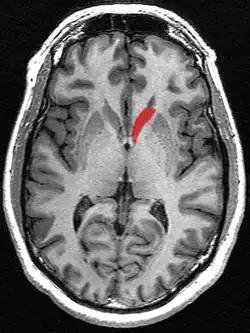

Caudate nucleus

Transverse cut of brain (horizontal section), basal ganglia is blue | |